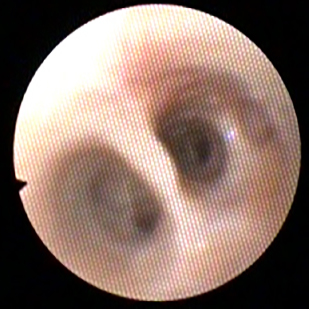

Diagnostiek

Het stellen van een diagnose kan soms net spoorzoeken zijn. Soms is het eenvoudig en soms is het lastig.

Onze diagnostische mogelijkheden hebben we uitgebreid door de aanschaf van vele soorten van apparatuur en het volgen van allerlei cursussen.